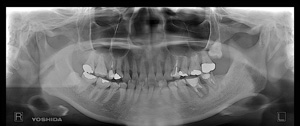

@@R.S‚³‚ñ@56Î —«  ‘åŠw‹³Žö @Žèp“ú@‚Q‚O‚O‚W”N ‚QŒŽ ‚X“úi“yj@㉺Š{  ƒm[ƒxƒ‹ƒKƒCƒhŽg—p@Ö¬“à’ÁÖ@•¹—p@@@

@@@@@ãŠ{  All on ‚U@‘¦Žž‰Ád@@

@@@@@@@@@@@@@ Rpl Tapered Rp  ‚P‚O mm(‚U–{)

@@@@@‰ºŠ{¶‰E@‘¦Žž‰Ád@ ‚R Unit Bridge@

@@@@@@@@@@@ @Rpl Tapered Rp  ‚P‚O mm(‚S–{)@@–ƒWƒ‹ƒRƒjƒAƒNƒ‰ƒEƒ“‚ÅÅI•â’Ô